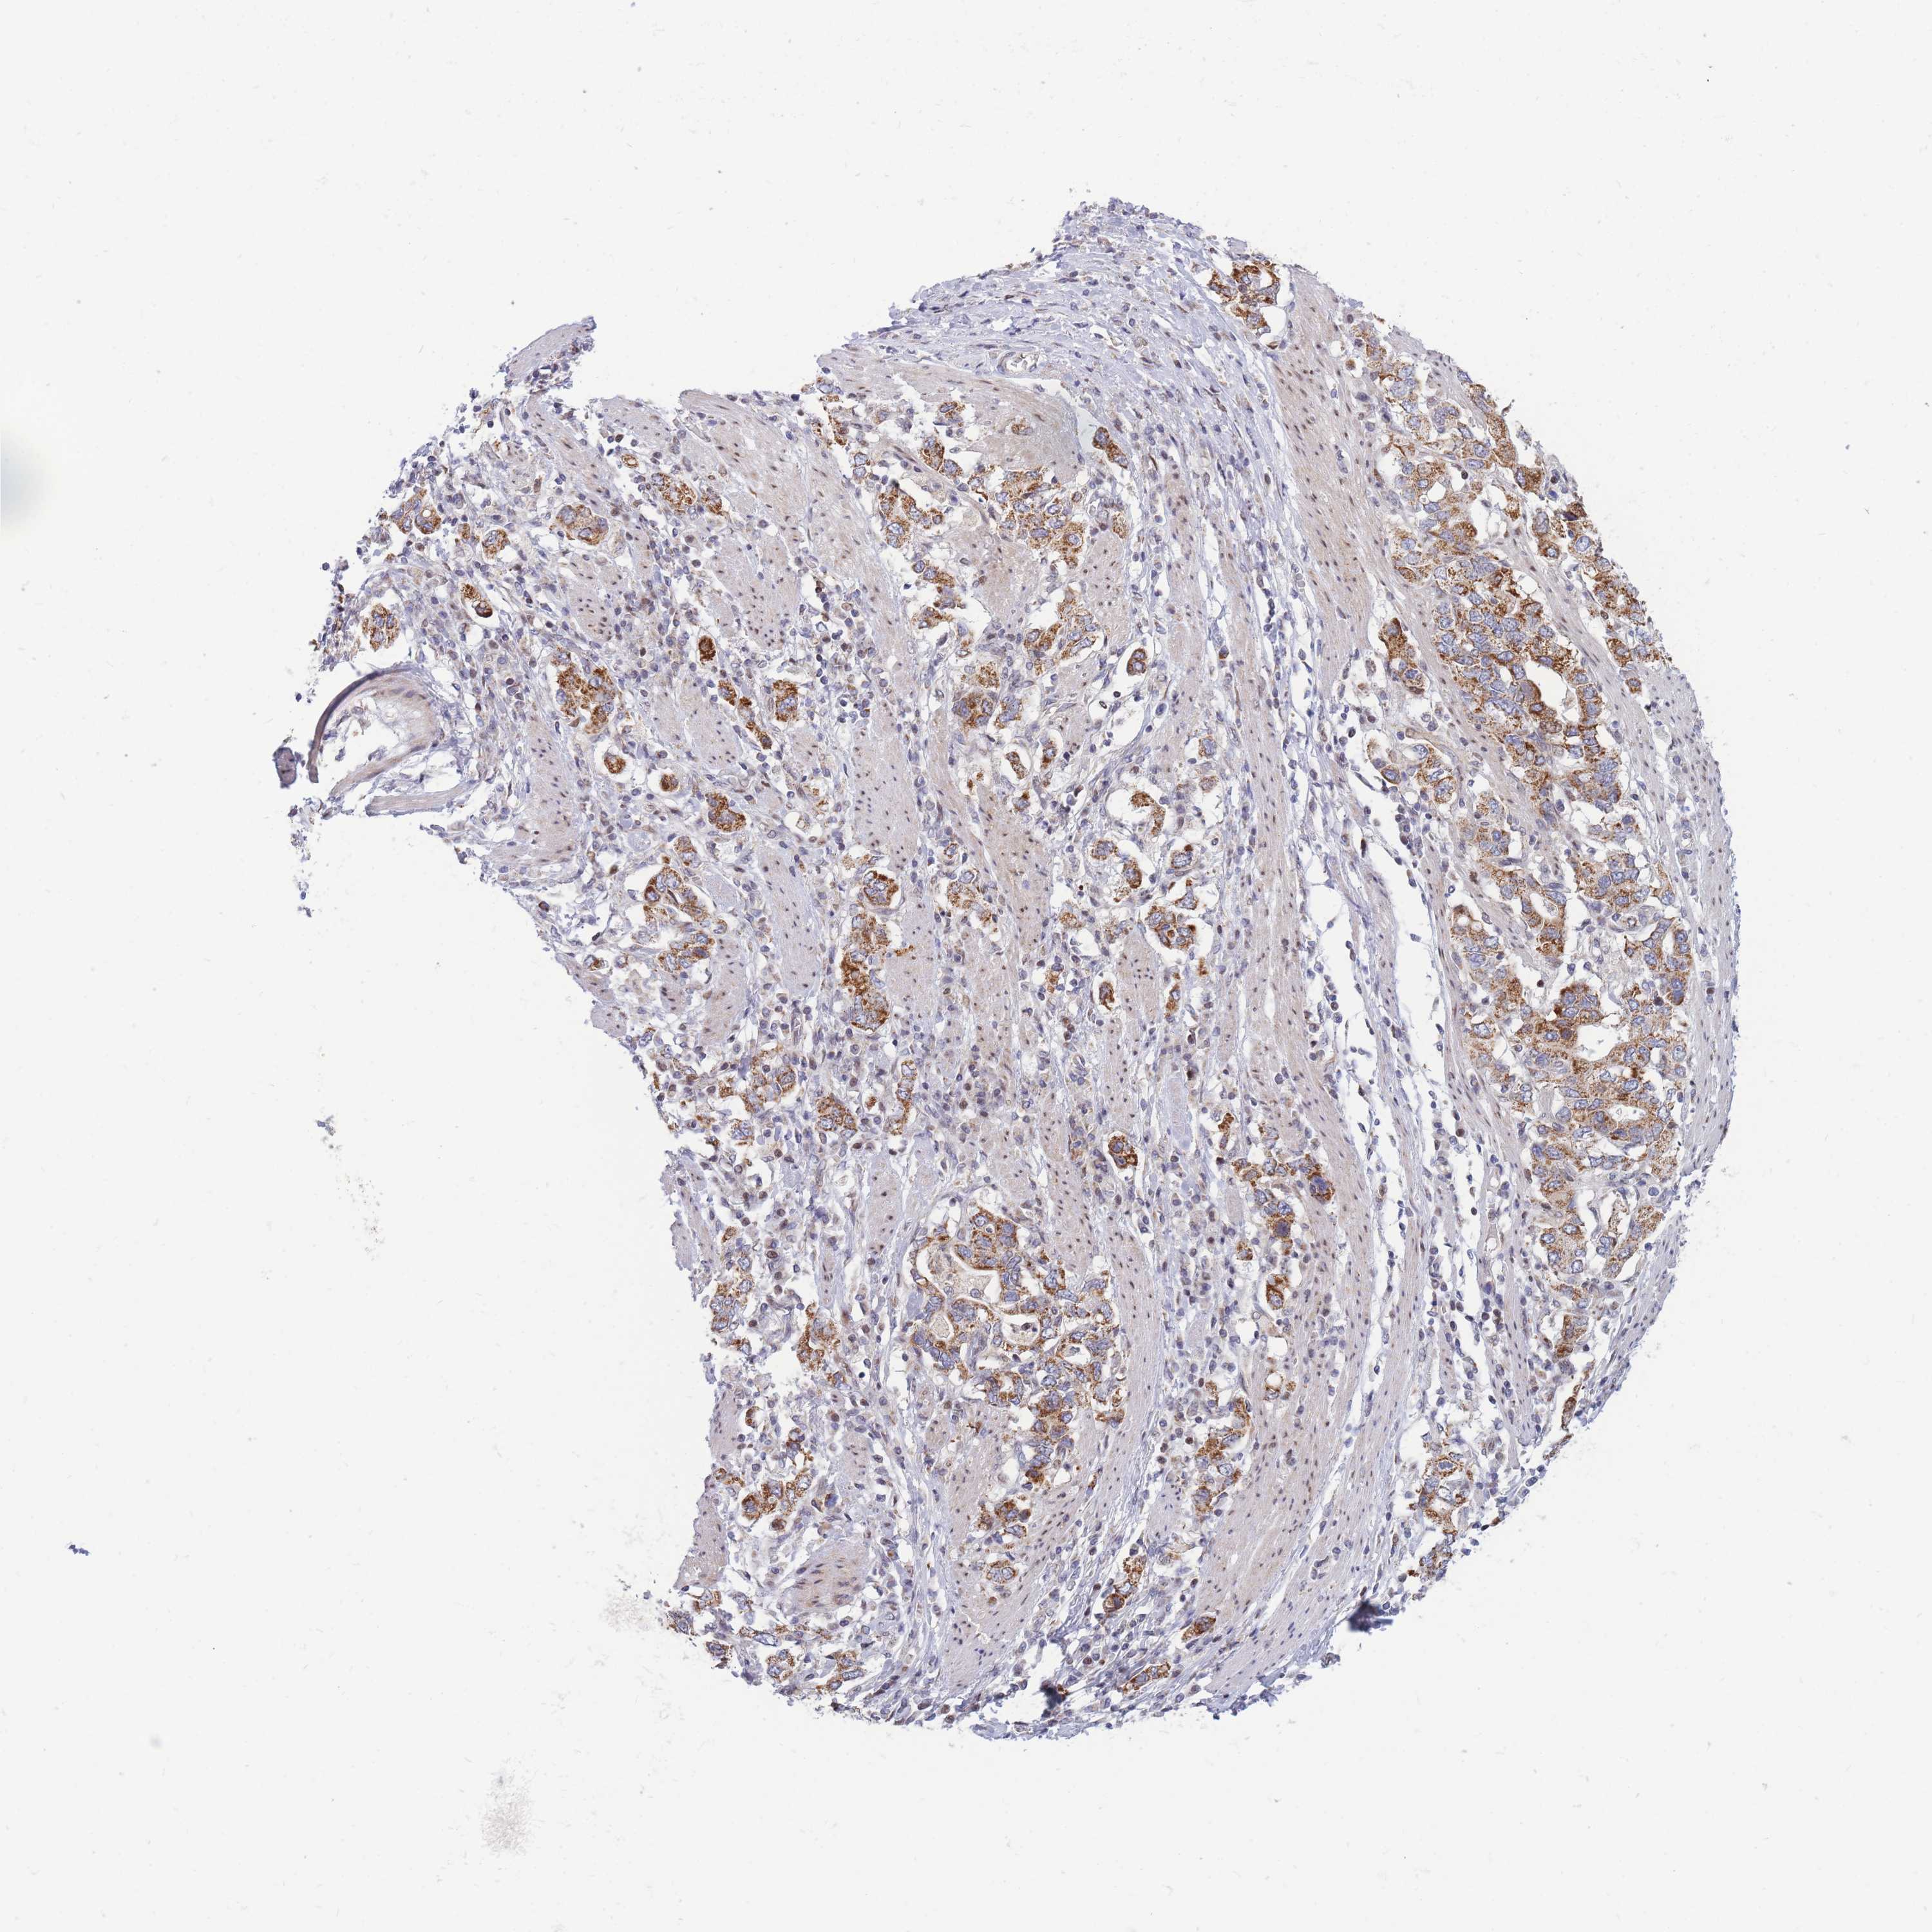

STOMACH CANCER - Protein expressioni

A mouse-over function shows sample information and annotation data. Click on an image to view it in a full screen mode. Samples can be filtered based on level of antibody staining by selecting one or several of the following categories: high, medium, low and not detected. The assay and annotation is described here.

Note that samples used for immunohistochemistry by the Human Protein Atlas do not correspond to samples in the TCGA dataset.

Antibody stainingi

Antibody staining in the annotated cell types in the current human tissue is reported as not detected, low, medium, or high, based on conventional immunohistochemistry profiling in selected tissues. This score is based on the combination of the staining intensity and fraction of stained cells.

Each image is clickable and will lead to virtual microscopy that enables deeper exploration of all samples and also displays staining intensity scores, fraction scores and subcellular localization as well as patient and tissue information for each sample.

Antibody HPA038755

Antibody HPA044125

Antibody HPA048272

Staining

High

Medium

Low

Not detected

Intensity

Strong

Moderate

Weak

Negative

Quantity

>75%

75%-25%

<25%

None

Location

Nuclear

Cytoplasmic/membranous

Cytoplasmic/membranous,nuclear

Adenocarcinoma, NOS